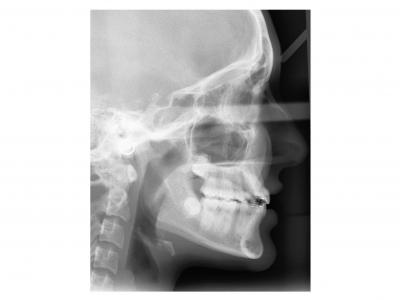

Ici, dans les deux cas, les deuxièmes prémolaires ont été extraites et les traitements ont duré 18 mois.

Dans le premier cas, la béance s'est fermée spontanément (pas prévu au départ) sans rééducation, sans appareil de contrainte linguale, ni élastique. Il semblerait que le gain de place a permis aux incisives de se redresser spontanément et donc de fermer la béance. La fermeture de la béance, la normalisation de l'environnement anatomique a permis à la langue de se mettre à travailler correctement. Pour le sens transversal, la correction a été aussi spontanée. Juste une minivis dans le secteur 1 a été placée pour recentrer mon milieu (ancrage maximal recherché au départ). Les finitions auraient pu être meilleures. Elle finit avec une légère classe II (on va dire qu’elle est surcorrigée :)). Le traitement a terminé plus tôt que prévu (24 mois annoncé), car problèmes de santé.

Dans le deuxième cas, le désencombrement a fermé les espaces en 6 mois. Les incisives ont été surtorquée pour avoir un meilleur soutien labial. Le traitement qui avait bien débuté, a été difficile à finir, car les anatomies coronaires et radiculaires étaient perturbées.

Si on n'avait pas extrait dans le premier cas, cela imposait une ouverture de l'espace de la 24 et donc une avancée des incisives supérieures et donc une aggravation de la béance. Dans le deuxième, on sortait les racines de l'os alvéolaires (racines déjà apparentes au départ). Même une expansion associée à du stripping et une distalisation des secteurs latéraux n’auraient pas permis de préserver ce parodonte fin.